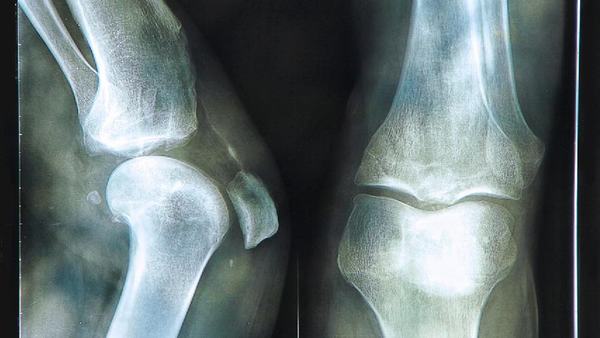

冬季要怎么样预防骨质疏松

首先,合理的饮食是预防骨质疏松的首要措施。在冬季,我们应该注重摄取富含钙和维生素D的食物,如乳制品、豆制品、海产品、绿叶蔬菜等。钙质是构成骨骼的重要成分,而维生素D有助于促进钙的吸收和利用。此外,我们还应该控制高盐、高糖和高脂肪等不健康的饮食习惯,避免过度摄入咖啡因和碳酸饮料。 其次,适量的户外活动对于骨质疏松的预防也起到重要的作用。寒冷的冬季容易使人们宅在家里,不愿意外出活动。然而,长时间的缺乏阳光和运动会导致钙的流失,从而加重骨质疏松的风险。因此,我们要适当增加户外活动的时间,每天至少晒太阳30分钟,进行适当的有氧运动,如散步、慢跑和太极等。这不仅有助于钙的吸收和骨骼生长,还可以增强肌肉和平衡能力,预防摔倒导致骨折的风险。 此外,保持良好的生活习惯也是预防骨质疏松的关键。我们应该避免烟草和酒精的滥用,因为它们会影响钙的吸收和骨骼的健康。此外,过度的压力和焦虑也会导致骨质疏松的发生,所以我们要保持良好的心态,学会放松自己。 最后,定期进行骨密度检查也是预防骨质疏松的重要措施。骨密度检查可以帮助我们及早发现骨质疏松的症状,并采取相应的治疗措施。特别是对于更年期的女性和长期使用激素的人群,骨密度检查尤为重要。 总之,冬季是骨质疏松的高发季节,我们要采取一系列的措施来预防骨质疏松的发生。合理饮食、适量户外活动、保持良好生活习惯和定期检查骨密度是重要的预防措施。让我们在寒冷的冬天里健康地度过,并拥有坚固健康的骨骼。